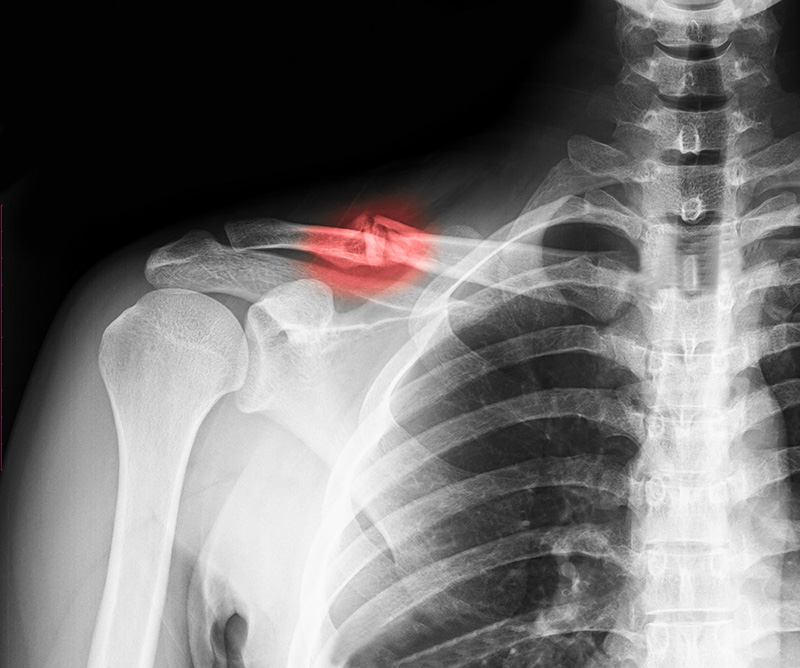

Chấn thương chỉnh hình là nhánh của y học chuyên điều trị các vấn đề liên quan đến:

Ngành này không chỉ bao gồm xử lý chấn thương do tai nạn hay vận động mạnh mà còn đánh giá và điều trị các bệnh lý mãn tính như thoái hóa khớp, viêm gân hay viêm bao hoạt dịch. Ngoài ra, chấn thương chỉnh hình còn liên quan đến phục hồi chức năng sau phẫu thuật hoặc sau chấn thương.

Do vận động mạnh, chơi thể thao hoặc tai nạn sinh hoạt. Bác sĩ sẽ đánh giá dây chằng, mô mềm và khớp thông qua siêu âm hoặc X-quang.

Tùy vào tình trạng, bác sĩ chỉ định chụp X-quang, siêu âm, CT hoặc MRI để đánh giá chi tiết tổn thương.